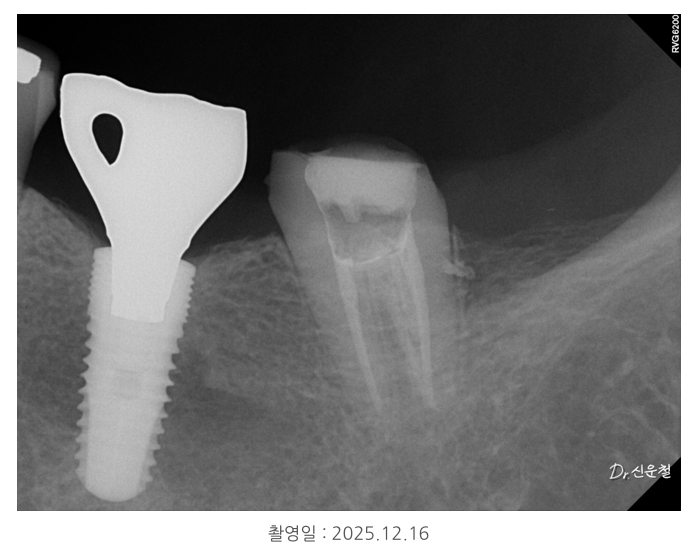

그래서 상태에 따라 기둥 보강(포스트)을 하고

그 위를 씌워 치아를 보호하게 됩니다.